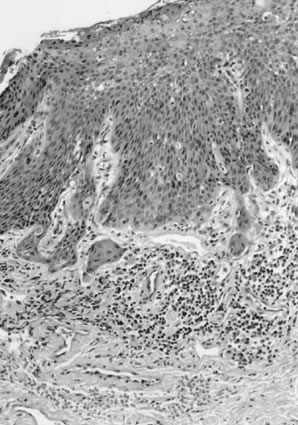

The FIGO staging of vulvar carcinoma has defined a stage IA subset of stage I carcinoma as originally set forth by the ISSVD, as a tumor with a diameter of 2 cm (20 mm) or less with a depth of invasion of 1 mm or less (Fig. 8). Measurement of tumor diameter alone is insufficient to define the risk of nodal metastasis. Most vulvar carcinomas with a depth of invasion of 1 mm or less are less than 2 cm in diameter. Clinically, VIN surrounding the tumor may be included erroneously in the measurement of the tumor diameter. In superficially invasive vulvar carcinoma, it is essential that the entire tumor be available for study before an attempt is made to determine the depth of invasion. Cases in which there is more than one tumor are not included in the stage IA group. The depth of invasion is defined as the measurement from the epithelial-stromal junction of the adjacent most superficial dermal papilla to the deepest point of invasion, as described by Wilkinson and colleagues.1,30,31 The ISGP and the WHO have accepted this definition of the “depth of invasion” in the vulva.1,2 This measurement should be distinguished from the “thickness of the tumor,” which is defined as the measurement from the surface, or bottom of the granular layer of keratin, if present, to the deepest point of invasion (Fig. 9A, B). The ISGP and WHO recommend that the pathologist report both measurements whenever possible. The stage IA group includes patients whose tumors involve capillary-like spaces, provided skin measurements are available. A protocol for the evaluation of vulvar specimens drafted by the senior author (Wilkinson) has been published by the College of American Pathologists.26

Fig. 8. Superficially invasive squamous cell carcinoma with vulvar intraepithelial neoplasia (VIN) 3. There is a marked inflammatory response.